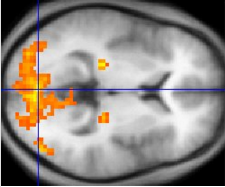

Détection par l'IRMf de l'activation des régions du cerveau impliquées dans la perception visuelle. Illustration: Wikimedia Commons

Financé par l'UE, le projet COLUMNARCODECRACKING a réussi à utiliser des scanners d'IRMf très poussés pour cartographier les colonnes corticales, un processus qui ouvre la voie à des nouvelles applications passionnantes, comme les interfaces cerveau-ordinateur.

L'IRMf corticale au niveau colonnaire a déjà contribué et contribuera à mieux comprendre la façon dont fonctionnent le cerveau et la pensée en se concentrant sur l'organisation fonctionnelle au sein de régions spécialisées du cerveau.